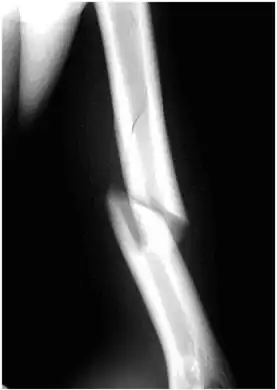

An x-ray image of a spiral fracture to the left humerus of a 27-year-old male. The injury was sustained during a fall.